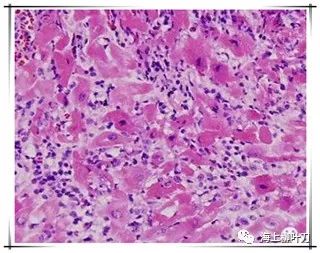

6.這是她的心肌病理切片,放大了100倍。

7.100倍還不是看得很清楚,放大400倍就很明顯了,一個個藍(lán)點就是淋巴球。這是很厲害的猛暴性心肌炎,整個心臟都被淋巴球浸潤了。